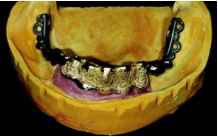

механической обработки литых деталей я использую только высококачественные фрезы марки Komet тип H364 RGE (GEBR. BRASSELER, Lemgo), применение которых не только позволяет обеспечить высокую эффективность фрезерования, но и гарантировать достижение оптимального качества фрезерованной поверхности. Особое внимание необходимо обращать на формирование оптимальной структуры пришеечных участков соединительной балки, а также тех участков поверхности опорных абат-ментов, которые располагаются над десной. Кроме того поскольку скорость и глубина фрезерования очень сильно зависит от марки и типа используемого инструмента, механическую обработку соединительной балки необходимо проводить таким образом, чтобы после ее завершения на пришеечных участках поверхности сохранился достаточно толстый слой золотого сплава, необходимый для надежной фиксации оригинальных абатментов. В связи с этим необходимо еще раз подчеркнуть, что любую механическую обработку первичных деталей можно проводить только после фиксации специальных вспомогательных приспособлений, что позволяет полностью исключить возможность случайного повреждения тех участков базовой поверхности абатментов, которые находятся в непосредственном контакте с имплантатами. После завершения фрезерования осуществ ляется финишное полирование поверхности окклюзии соединительной балки до зеркального блеска. Все остальные участки ее поверхности должны остаться неполированными, что значительно облегчает проведение предварительной примерки, стыковки и коррекции структуры вторичной конструкции. Внешний вид полностью готовой соединительной балки после завершения процесса фрезерования и финишного полирования поверхности окклюзии наглядно продемонстрирован на рисунке 15. Я абсолютно уверен в том, что полировать следует только нефрезерованные участки поверхности. Исходя из собственного практического опыта, я могу с полным основанием утверждать, что полирование фрезерованных поверхностей, как правило, приносит значительно больше вреда, чем пользы. На виде со стороны поверхности окклюзии (рис. 16) отчетливо видно, что в области зуба 43 верхний край соединительной балки располагается практически на том же уровне, что и головка постоянного фиксирующего винта. Вторичная конструкция Перед тем как приступать к изготовлению вторичной конструкции, на рабочей модели проводится заключительный контроль взаимного расположения соединительной балки и зубного ряда будущей реставрации (рис. 17). На этом снимке отчетливо видно, что благодаря формированию оптимальной структуры балки нам удалось значительно улучшить исходную клиническую ситуацию. Серьезные проблемы наблюдаются только в области зуба 43. В то же время совершенно очевидно, что для их решения достаточно немного уменьшить толщину язычной стенки вторичной конструкции: до минимума сократить толщину золотого каркаса и сохранить небольшой «золотой островок» на язычной поверхности полимерного базиса протеза. Si-tec-каркасы На следующем этапе осуществляется выбор оптимальной позиции для фиксации металлических способных к литью каркасов дополнительных ретенционных Si-tec-эле-ментов (фирмы Wegold). Для этого чрезвычайно целесообразно использовать диагностическую модель реставрации, поскольку с ее помощью можно очень быстро обнаружить те участки, на которых между

Ретенционные перлы еще не нанесены. очень широкая кромка будущего золотого каркаса, наличие которой, с одной стороны, позволяет значительно повысить стабильность внешней конструкции (образование характерного Т-профиля), а с другой стороны сформировать идеальные условия для обеспечения высокого уровня гигиены тканей пародонта в области имплантации (в непосредственной близости от имплантатов слизистая оболочка полости рта контактирует только с отполированной до зеркального блеска базовой поверхностью золотого каркаса). Кроме того это значительно облегчает формирование гармоничного плавного перехода от поверхности золотого каркаса к поверхности полимерного базиса протеза. Само собой разумеется, что при использовании такой технологии форма внутренней поверхности внешней кромки каркаса должна с высокой точностью отражать все особенности строения десневой маски и прилегающих мягких тканей. Только что отлитый золотой каркас после удаления формовочной массы (пескоструйная обработка при пониженном давлении и кислотное травление) представлен на рисунке 19. На увеличенном снимке каркаса со стороны базовой поверхности (рис. 20) отчетливо видны прекрасно интегрированные каркасы дополнительных ретенционных Si-tec-элементов. Кроме того при анализе этого снимка особое внимание необходимо обратить на великолепное качество внутренней поверхности необработанного литого каркаса. Интеграция Si-tec-каркасов в структуру металлического каркаса вторичной конструкции является неотъемлемой составной частью моей философии изготовления съемных реставраций. При этом в подавляющем большинстве случаев установка этих каркасов осуществляется исключительно в профилактических целях: в качестве подготовки к возможной последующей фиксации TK-Snap-элементов. В нормальных условиях стабильность реставрации обеспечивается за счет образования прочного фрикционного контакта между фрезерованными поверхностями соединительной балки и золотого каркаса вторичной конструкции. Однако при изготовлении съемных реставраций обязательно необходимо учитывать тот факт, что в процессе их эксплуатации может произойти преждевременная утрата одного или нескольких опорных им-плантатов, что удаление части соединительной балки неизбежно приводит к значительному снижению площади фрикционного контакта, а следовательно, и стабильности внешней конструкции. В таких случаях установка одного или нескольких TK-Snap-элементов позволяет значительно повысить прочность фрикционного контакта, а следовательно, и стабильность съемной части протеза без какой-либо дополнительной коррекции его структуры. Финишная обработка После завершения предварительной примерки каркаса вторичной конструкции, а также проведения соответствующей коррекции его